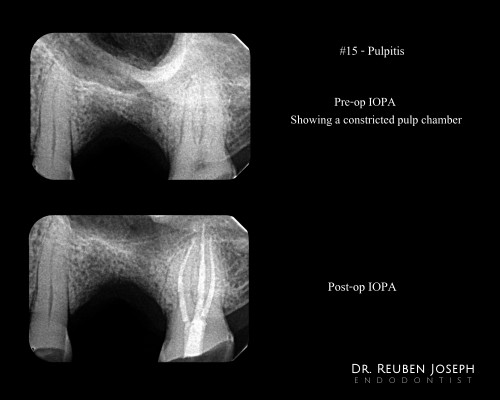

#15 Pulpitis – Canal Projection

By Reuben Joseph / June 26, 2018

Pre-op Assessment: Severe attrition and a constricted pulp chamber. Treatment plan: Access cavity planned taking […]